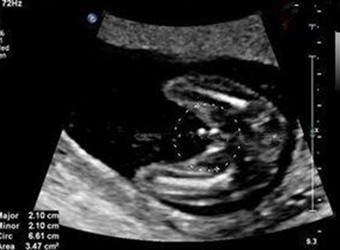

怀孕五个月的B超图来看,可以清楚的看到,此时胎儿的耳朵已微微张开,头发和眉毛已经开始生长,牙床开始形成。手指和脚趾开始隆起,并长出指甲。有时候,他还…